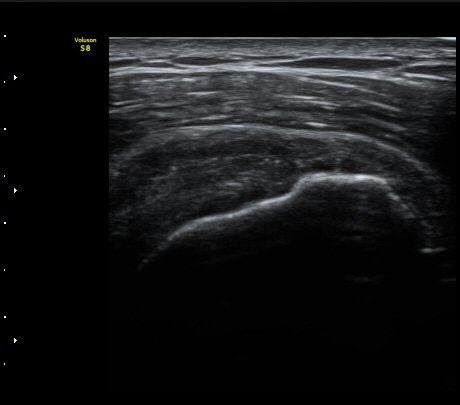

ÃÊÀ½ÆÄ °Ë»ç

À̵ιڱ٠Ⱦ´Ü¸é°Ë»ç¿¡¼­ Á¤¸Æ³¶ÀÇ ºÎÁ¾ÀÌ °üÂûµÊ(±×¸² 1).

±Ø»ó°Ç³»Ãø Á¾´Ü¸é°Ë»ç¿¡¼­ ±Ø»ê°Ç ºÎÂøºÎÀÇ  ÀÛÀº ÆÄ¿­°ú Á¡¾×³¶ ºÎÁ¾ÀÌ °üÂûµÊ(±×¸² 2, 3).

±Ø»ó°Ç ¿ÜÃø Á¾´Ü¸é°Ë»ç ½Ã Á¡¾×³¶ ºÎÁ¾ÀÌ °üÂûµÊ(±×¸² 4).

±Ø»ó°Ç ±ÙÀ§ºÎ ±Ø»ó°Ç ³»ÃøÀÇ Àú¿¡ÄÚ ºÎÁ¾°ú Á¡¾×³¶ ºÎÁ¾ÀÌ °üÂûµÊ(±×¸² 5).

±Ø»ó°Ç ¿øÀ§ºÎ ±Ø»ó°Ç ºÎÂøºÎ ÀÛÀº ÆÄ¿­ÀÌ °üÂûµÊ(±×¸² 6).

ŽÃËÀÚ¸¦ °ßºÀ ¿ÜÃø¿¡ ´ë°í ÆÈÀ» ¿ÜÀüÇϸ鼭 ´ë°áÀý°ú °ßºÀÀÇ Ãæµ¹À» °üÂûÇÏ´Ï °ßºÀ¿ÜÃø¿¡

¼ö¾×ÀÌ Àú·ùµÇ¾î ¿ÜÃø Ãæµ¹ÁõÈıºÀÌ È®ÀεǾú´Ù(÷ºÎ ÆÄÀÏ 1).